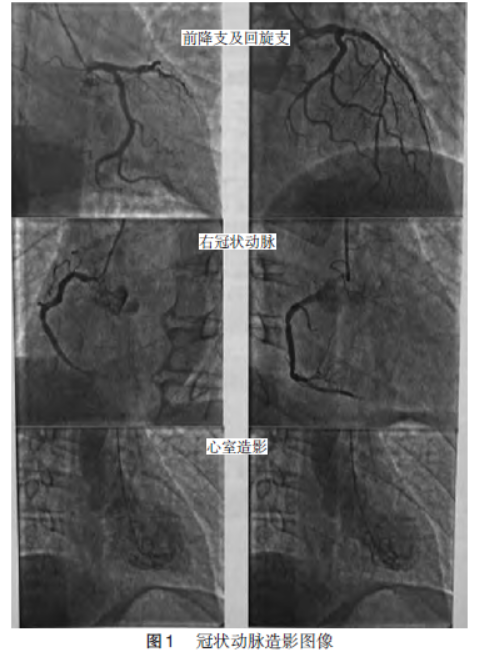

考虑患者为急性ST段抬高型心肌梗死,急性左心力衰竭可能大。给予无创呼吸机辅助通气,口服替格瑞洛180mg、阿司匹林300mg,静脉注射泮托拉唑40mg抑酸、呋塞米20mg利尿治疗,持续静脉输注硝酸异山梨酯2mg/h扩张冠状动脉。入心内导管室行急诊造影检查,术中可见冠状动脉狭窄最大50%,左心室大小及厚度正常,心底部运动相对增强,前壁及下壁近心尖部不运动,心尖钝圆,收缩期轻度外凸,LVEF30%,考虑为应激性心肌病,见图1。